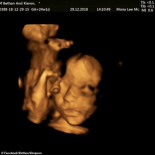

Método pionero: Abren el útero de la madre para operar al bebé, que nacerá meses después

espina bifida

operación

útero

feto